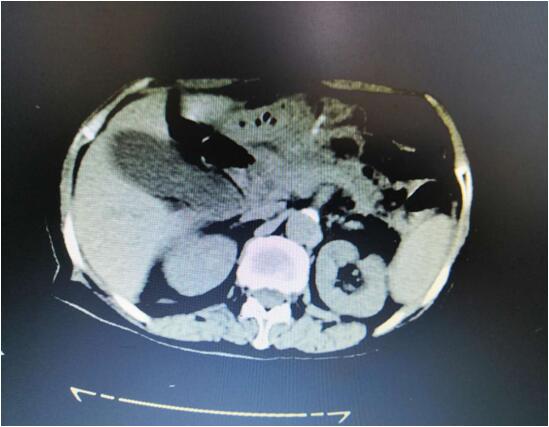

患者B,女,51歲,因牙齦出血1年入院,入院診斷為:乙肝,肝炎后肝硬化,門脈高壓癥,巨脾,脾亢,白細胞、血小板減少,中度貧血。5年前,曾在外院行介入脾栓塞術,脾臟不僅沒有縮小,反而越來越大,脾下緣已經(jīng)超過腹部正中線、抵達臍部,就像幾個月“身孕”的婦女,給病人帶來巨大身心負擔。

(術前腹部CT顯示巨脾)